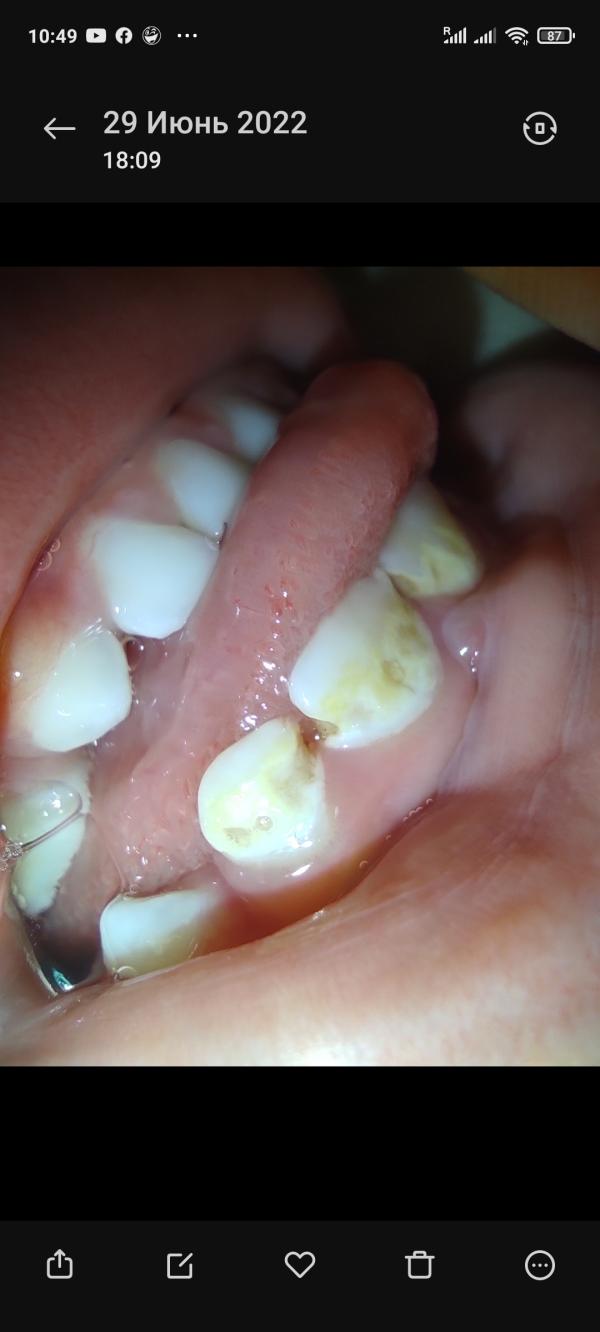

Фото прикрепряю(смотрите дату с какой скоростью портятся зубки)

Они становились жёлтые, фото буду прикреплять. Тут стоматологи говорят очень разные предположения. То флюороз, то кариез, я не знаю что думать и чем лечить. Флюороз - переизбыток фтора(в польше мы купили детскую зубную пасту, в составе был фтор, он предотвращает кариез), Кариез - сказали что начальная стадия, зубки портятся из-за того что грудное молоко остаётся под губой, лечить сказали так:"чаще чистить зубки пастой с ФТОРОМ"

У меня патовая ситуация, 2 варианта, один из них - убьёт зубы. Но это малость моих проблем уже. Вчера вечером мы пошли в детскую комнату, дети играли, и Милош ударился зубами об горку, в итоге минус половина переднего зуба. Стоматолога(детского!) в нашем городе нет, только в поликлинике(он сказал кариез)

Мы лечили в Польше когда была ситуация как на первом фото, сказали кариес в начальной стадии